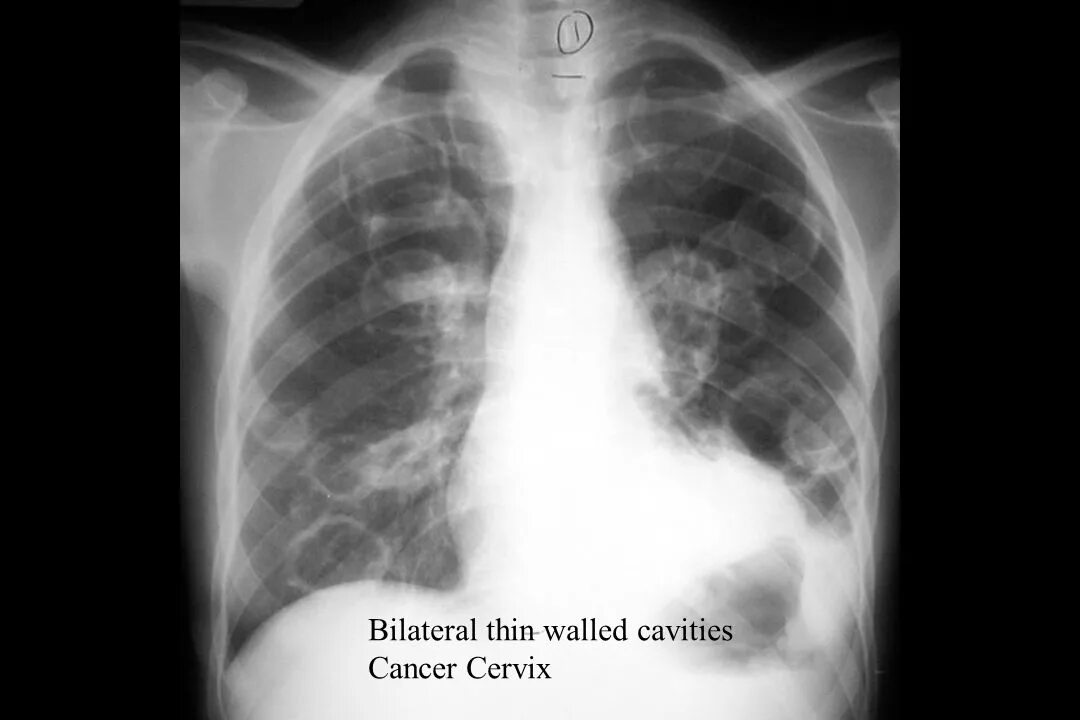

Метастазы у ребенка